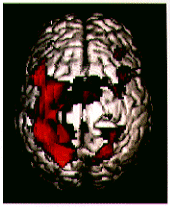

図1 左手複雑指手運動負荷を用いたfMRI。頭頂から見た大脳皮質三次元像と賦活部位を合成。複雑指手運動に伴う右一次感覚性運動野、両側前運動野、補足運動野の賦活が確認される。

(原論文1より引用)

被検者に少し複雑な指手運動負荷を行わせることで一次感覚性運動野以外に前運動野、補足運動野に賦活が確認される。脳腫瘍症例でも、手の運動負荷により中心溝の同定が容易となり、腫瘍と一次感覚性運動野の位置関係が理解される。